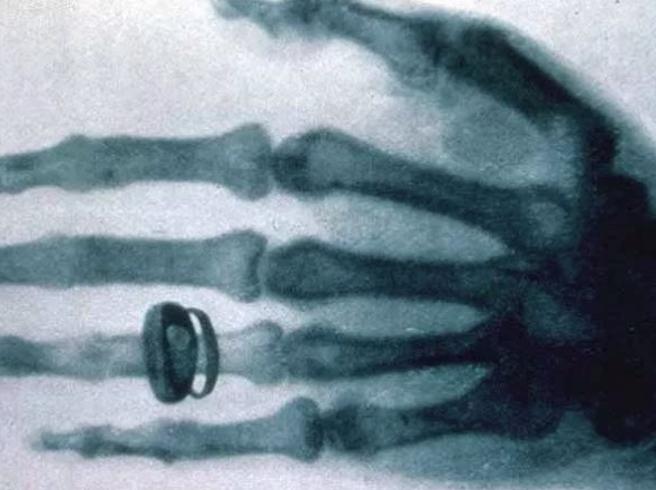

1896 – Viene mostrata la prima macchina a Raggi X